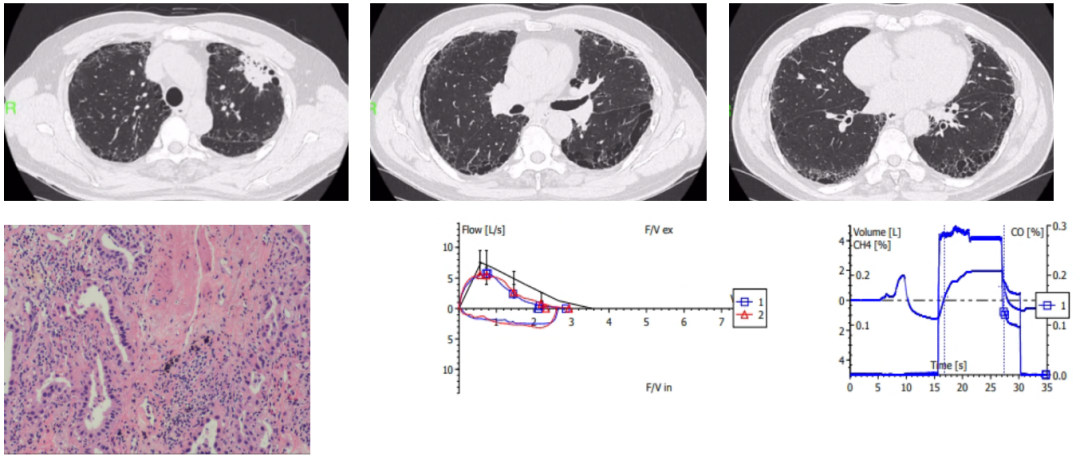

术中快速现场细胞学(ROSE)提示以巨噬细胞为主的炎症细胞浸润,初步判断为感染性病变。进一步活检组织病理提示大量CD68⁺巨噬细胞浸润,胞质内见Michaelis-Gutmann小体(钙铁沉积包涵体),免疫组化:CD163(+),CD56(-),CD68(+),CgA(-),CK5/6(-),CK7(-),Ki67(约10%~15%+),NapsinA(-),P40(-),S-100(散在+),Syn(-),TTF-1(-),PAS染色阳性,符合气道软斑病表现。组织培养及组织宏基因组测序(NGS)提示大肠埃希菌感染,序列数15138,相对丰度35.65%(图5)。结合患者双肺移植术后免疫抑制状态,修正诊断为:

image.png

图5 ROSE提示以巨噬细胞(红色箭头)为主的炎症细胞浸润;组织病理提示大量CD68⁺巨噬细胞浸润,胞质内见Michaelis-Gutmann小体(红色箭头),组织培养及组织宏基因组测序(NGS)提示大肠埃希菌感染,序列数15138,相对丰度35.65%

抗感染治疗:初始予以莫西沙星0.4 QD抗感染,后效果欠佳,改为亚胺培南/西司他丁1.0 Q8H(根据药敏结果,该患者为ESBL+,左氧氟沙星耐药,图6)。

气道介入治疗:多次行支气管镜下高频电刀联合冷冻治疗(图7)清除病变,改善气道通畅性。

图7 支气管镜下圈套切除及冷冻治疗后管腔通畅